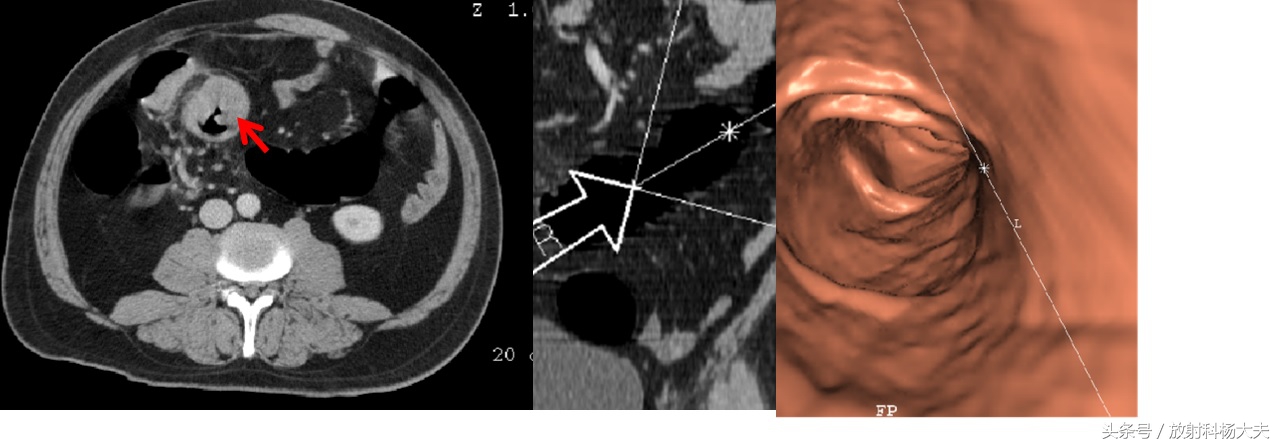

又叫虚拟结肠镜,CT结肠造影等。跟结肠镜比,CT结肠镜不需要插管子。只需要经过肠道准备(与结肠镜类似),病人躺在CT检查床上,经直肠注入一定量气体,让肠道充盈,然后进行仰卧和俯卧位两次CT扫描即可。后续的工作就是大夫和计算机的事了,通过计算,形成一种类似结肠镜观察到的影像,借此进行疾病的检查和诊断。